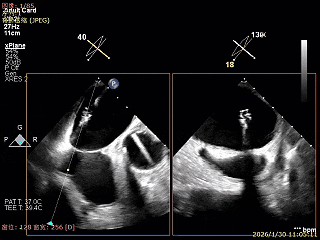

Bicomm切面看2区脱垂

上Color,可见反流主要来自于3区

X-Plane切面切1区未见明显异常

1区上Color,未见反流来源

X-Plane切面切2区可见前叶Flail

2区上Color,可见反流来源

X-Plane切面切3区可见前叶脱垂

3区上Color,可见反流来源

3D Enface 2区及3区前叶脱向左房

3D Enface 可见反流由2区3区从前后冲出